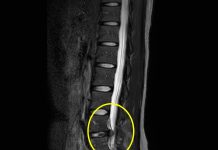

偏頭痛的病因雖仍無法肯定,主要的病理解釋是:大腦皮層的興奮度增強,以及腦幹中三叉神經核裡的神經元的痛感控制異常。至少可確定是腦部血管活動異常所引起,包括軟膜動脈、硬膜動脈和顱外動脈,屬於神經性血管疾病。